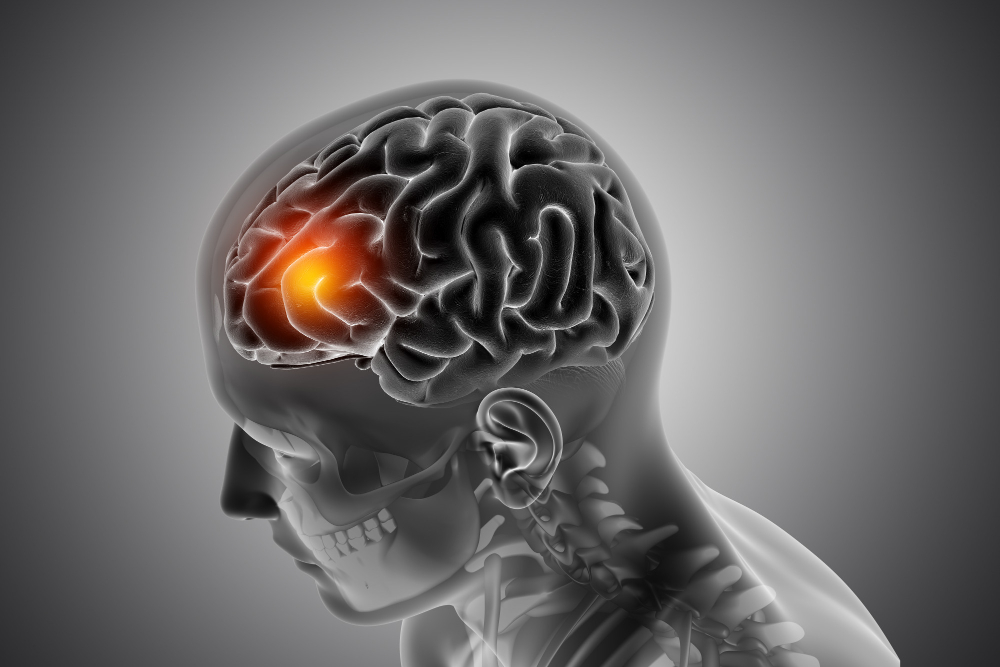

• Mental Tension

Mental Tension, Anxiety Disorder, Mood Disorder, Depression, Phobia, Sleep Disorder, Insomnia, Tremor, Parkinson and all old age complaints, etc...

• Neurological Problem

Neurological Problem Trigeminal Neuralgia, Neuritis, Neuropathy, Muscular Dystrophy, Multiple Sclerosis.